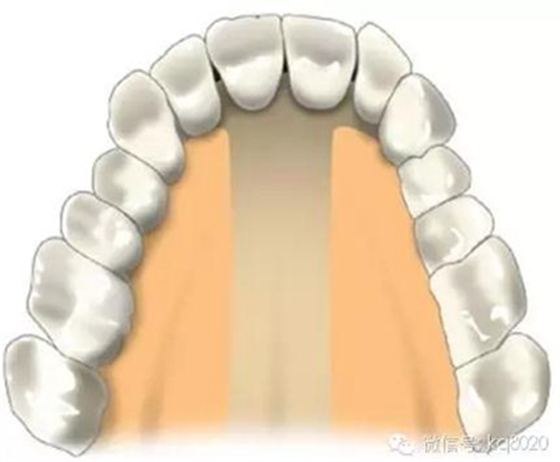

根據(jù)骨類型,骨密度,牙根間距、粘膜厚度不同,把上下頜分為不同區(qū)域,分別用紫橙藍(lán)黃四種顏色標(biāo)記,這些區(qū)域就是傳統(tǒng)的可植入部位,每個(gè)部位所選擇的支抗釘也相應(yīng)會(huì)有所差異

上下頜前牙區(qū)(11、12或者23之間,具體根據(jù)CT和患者頜關(guān)系決定):

危險(xiǎn)因素:此處無重要血管神經(jīng),相對安全,但牙根間距較小,避免傷及牙根植入位置和角度:應(yīng)從膜齦聯(lián)合處或其牙合方植入,大約距離牙槽嵴頂5-6mm的位置,

②避免植入后粘膜覆蓋;支抗釘位于牙根之間,與牙體長軸成30-45°角

大小:由于前牙區(qū)牙根間距小,骨質(zhì)疏松,宜選用6×1.4mm,且無切削尖設(shè)計(jì)支抗釘